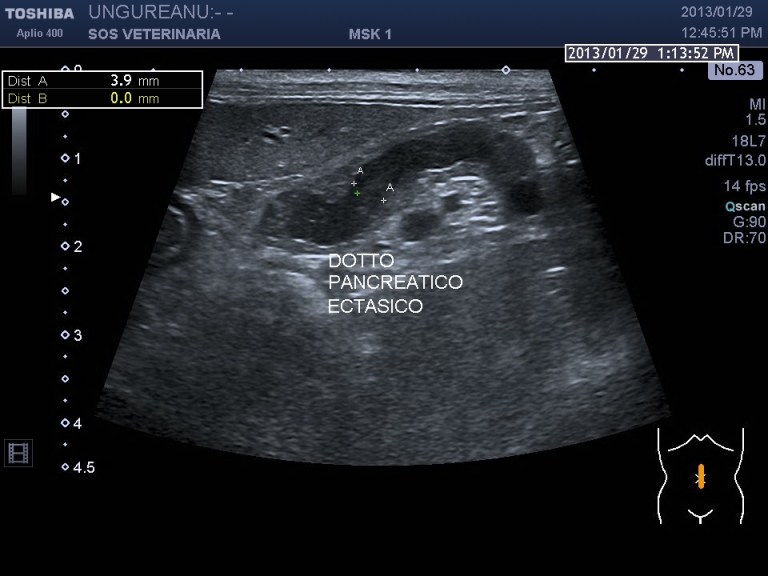

infiltrazione diffusa perironeale di immunoblasti ,ispessimento  mucosa intestinale-dilatazione coledoco -dotti pancreatici-calcolosi biliare intra epatica ed extraepatica

Rispetto il precedente caso la paipilla duodenale  e’ normale nella forma e nelle dimensioni ,sebbene affetto da calcolosi non si visualizzano calcoli nel coledoco o a livello della papilla che giustifichino la dilatazione delle vie biliari extraepatiche e pancreatiche  ,colpisce l’ispessimento del duodeno (5 mm contro un v.n. di 2,5 )  l’ectasia del dotto pancreatico, la stasi del succo pancreatico  e la diffusa presenza di strutture nodulari isolate o confluenti riferibili tessuto linfatico iperplastico  con un infiltrato di immunoblasti predominante .

La distensione delle vie biliari e pancreatiche puo’ essere secondaria al processo infiltrativo duodenale o a complicanza infiammatoria -settica comune nella specie felina (vedi triatide)  ,le interazioni sono molteplici ,la stessa calcolosi risulta severa con aspetti di colastasi intraepatica. Questo soggetto avrebbe avuto bisogno di approfondimenti e da destinarsi ad approfondimenti oncologici ,purtroppo anche in questo caso i proprietari non hanno voluto dar seguito al naturale iter diagnostico e terapeutico che il caso imponeva .